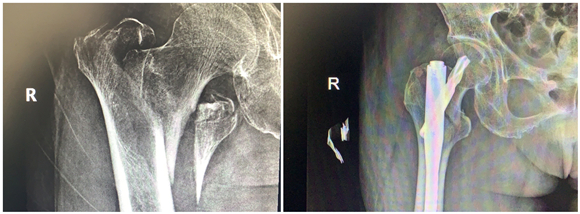

年前,蔡奶奶在家摔了一跤,右側(cè)股骨劇烈疼痛,不能走路,無(wú)法動(dòng)彈。檢查發(fā)現(xiàn)老人右側(cè)股骨粗隆間骨折,當(dāng)時(shí)老人拒絕治療,回家臥床后每況愈下。家人不忍心看著老人這么痛苦,了解到該院骨科擅長(zhǎng)老年性骨折治療,于是帶著老人來(lái)到該院鼓山路院區(qū)骨科就診。來(lái)院后,患者診斷為右股骨粗隆間粉碎骨折,并伴有右下肢深靜脈血栓、褥瘡、肺部感染等并發(fā)癥,情況非常危險(xiǎn),此類(lèi)骨折又稱(chēng)為“死亡骨折”。據(jù)了解,“死亡骨折”是指老年人的髖部骨折,常常是股骨粗隆間骨折和股骨頸骨折,其中骨折后臥床引起的并發(fā)癥會(huì)導(dǎo)致死亡,死亡率高達(dá)40%,又稱(chēng)人生最后一次骨折。

此類(lèi)手術(shù)風(fēng)險(xiǎn)大,醫(yī)生在告知患者家屬手術(shù)風(fēng)險(xiǎn)、術(shù)后康復(fù)、搶救方案等情況后,家屬打消了顧慮,決定盡快給老人家安排手術(shù),擺脫病痛折磨。同時(shí),麻醉科為老人制定了個(gè)性化的麻醉方案。王斌手術(shù)團(tuán)隊(duì)給患者制定了微創(chuàng)手術(shù)方案,通過(guò)三個(gè)小孔來(lái)進(jìn)行固定,避免了大的手術(shù)切口,整個(gè)手術(shù)過(guò)程僅僅耗時(shí)50分鐘,出血量50ml左右。

患者術(shù)后第二天就下地站立行走,X線(xiàn)顯示骨折對(duì)位好,復(fù)查下肢靜脈B超提示少許肌間靜脈血栓。在專(zhuān)科醫(yī)生的康復(fù)指導(dǎo)下,患者褥瘡、肺部感染也很快消失了。術(shù)后第7天,患者康復(fù)出院。